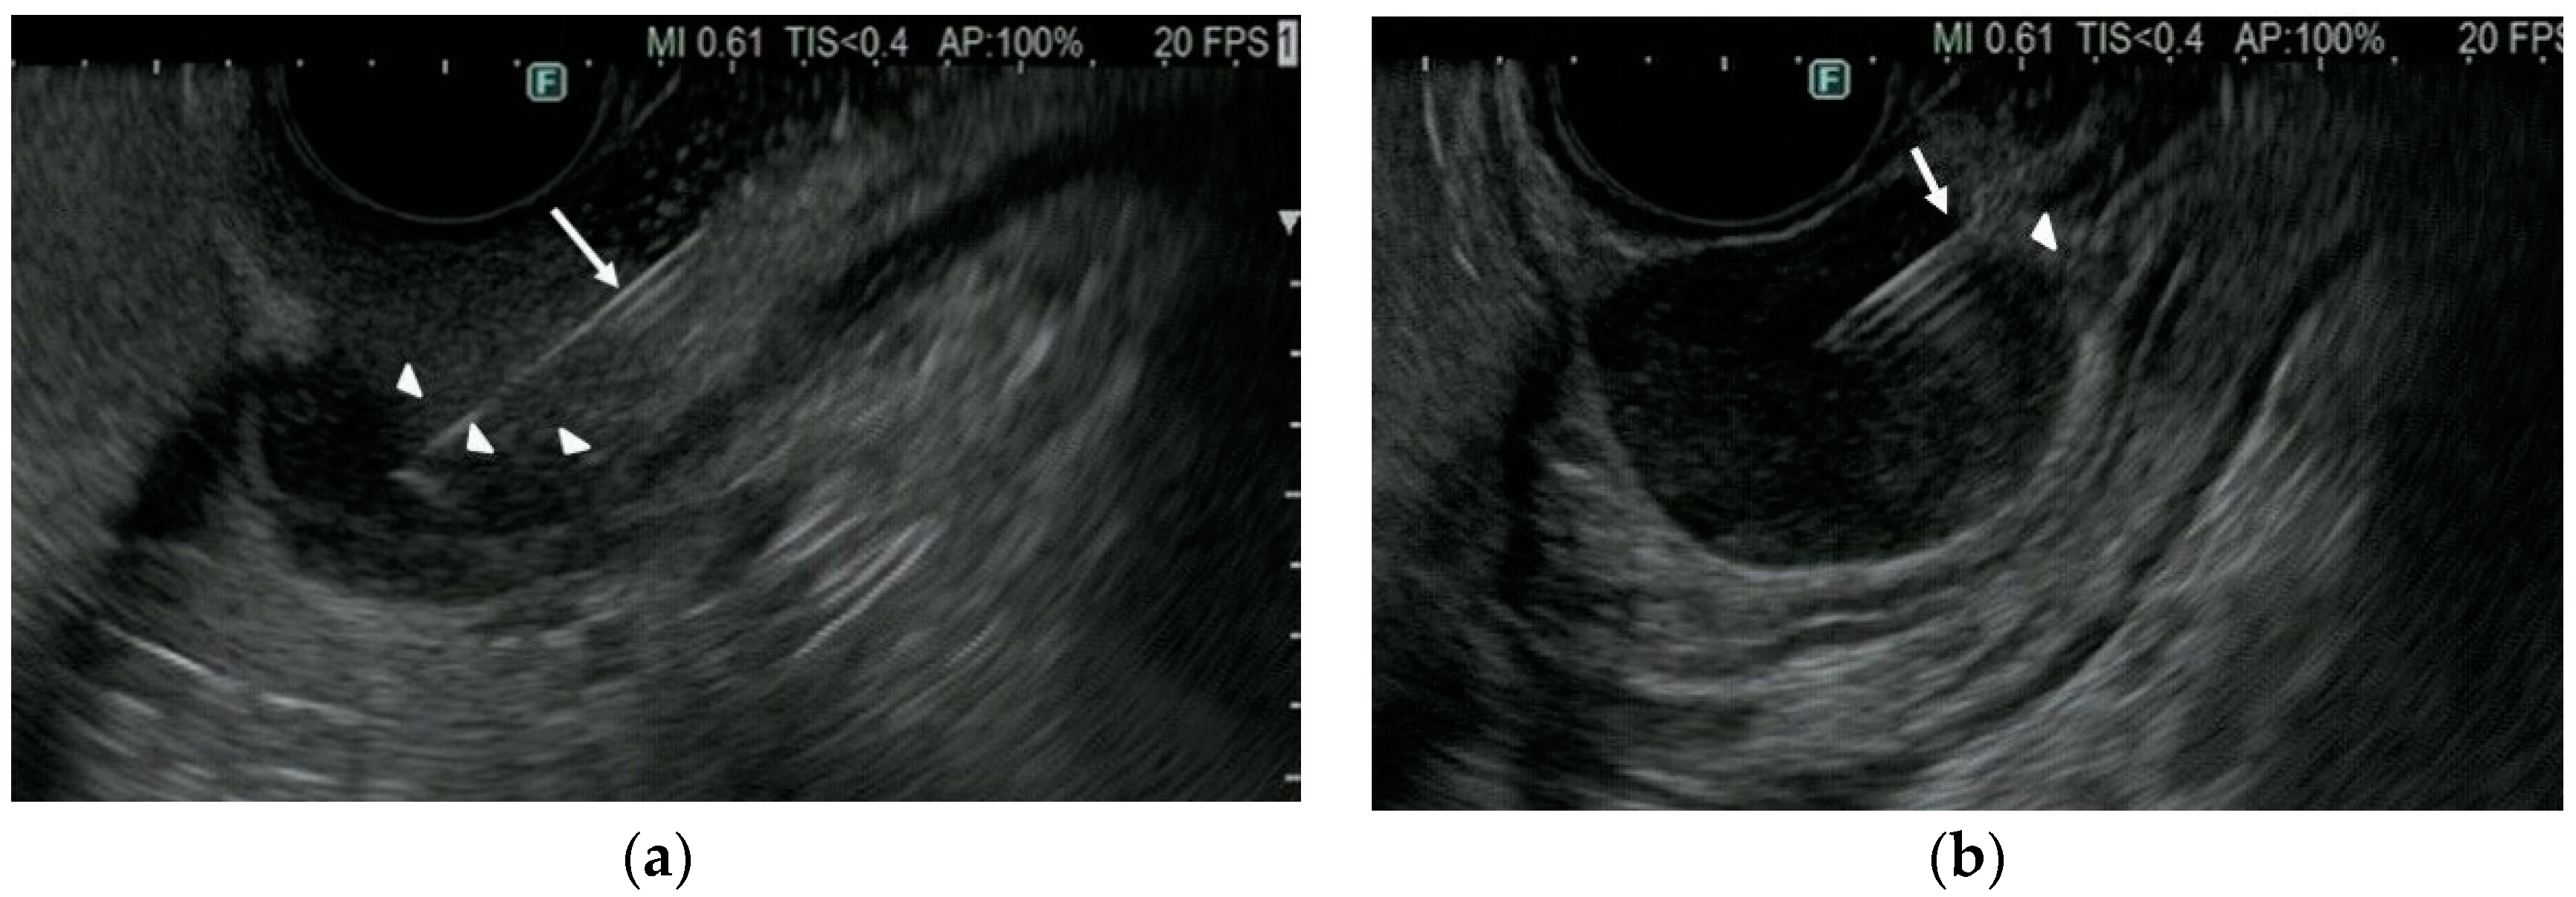

| Hyper- or iso-enhancement pattern on CH-EUS | 29 | 5 |

| Hypo-enhancement pattern on CH-EUS | 2 | 11 |